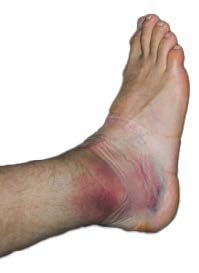

| 足踝內翻扭傷 |

外側翻踝腫痛 |